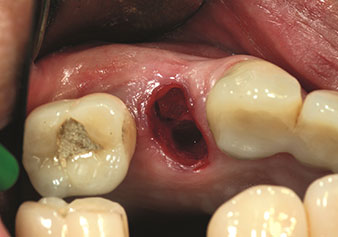

Eine oft unterschätzte Anwendung ist die schonende Extraktion von Zahnwurzeln oder auch von Wurzelfragmenten im Rahmen des Alveolenmanagements. Mit den feinen Periotomen, die aktuell in zwei Ausführungen (EX1 und EX2 von W&H) zur Verfügung stehen, lassen sich auch speziell endodontologisch vorbehandelte Zähne oder ankylosierte Wurzeln mühelos entfernen. Das Ergebnis sind Extraktionsalveolen, deren Hart- und Weichgewebe völlig intakt sind, da in der Regel auf ein Aufklappen verzichtet werden kann.

Dies stellt anschließend eine optimale Basis für eine spätere oder Sofortversorgung mit Implantaten dar (Abbildung eins und zwei mit freundlicher Genehmigung von Dr. Torsten Conrad, Bingen a. Rhein).

Zustand nach Extraktion mit Piezochirurgie

Abb. 2: Zustand nach Extraktion mit Piezochirurgie. Foto: © Dr Torsten Conrad (Bingen am Rhein)